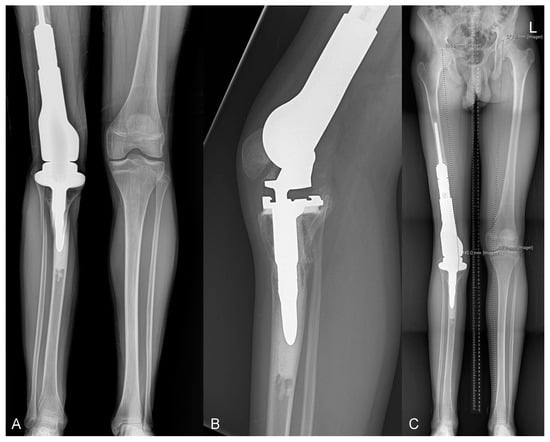

2.2. Type 2 Failures—Loosening and Nonunion

2.2.1. Endoprosthetic Aseptic Loosening